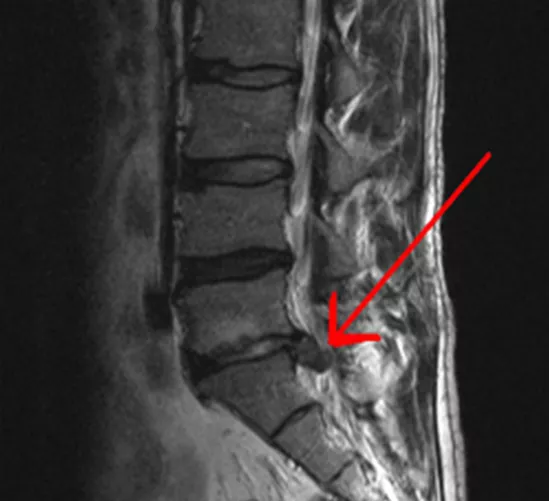

A gerincoszlop csigolyáit elválasztó porckorongoknak igen fontos szerepük van a gerinc egészséges működésében, tehermentesítésében. A porckorongok mindegyike egy erősebb külső, és egy puhább belső részből áll. A puha rész biztosítja a gerinc rugalmasságát, terhelhetőségét. Ha a porckorongok degenerálódnak, a puhább belső rész előreboltosulhat, kitüremkedhet, vagy áttörhet a kemény külső rétegen.

A porckorongnak ez a kiszakadt része nyomhatja, ingerelheti, sőt meg is sértheti az ideggyököket. A beteg ilyenkor attól függően érez a különféle testtájain (nyak, hát, derék, végtagok) fájdalmat, illetve izomgyengeséget, zsibbadást, esetleg attól függően válik érzéketlenné valamely végtagja, hogy hol történt a porckorongszakadás. Míg az izomgyengeség, zsibbadás, érzékvesztés elsősorban a végtagok valamelyikét érinti, addig a fájdalom nem csak a nyak-, hát- vagy deréktájon jelenik meg, hanem az ülőideg mentén is kisugárzik.

Az ilyen porckorongsérv - vagy ahogy a köznyelvben jobban ismert: gerincsérv - akadályozhatja a hólyag- és bélműködést is, ezért sürgős orvosi beavatkozásra lehet szükség.

Ha a derékfájás tünetei súlyosbodnak (pl. a fájdalom lesugárzik az alsó végtagba, zsibbadás, érzékelési zavar, reflexeltérés jelentkezik, vagy izomműködési zavarok lépnek fel), felmerülhet a porckorongsérülés, azaz a porckorongsérv gyanúja.

Mindezen ismeretek birtokában kerülhet sor a fizikális, azaz a tapintásos (a reflexeket, az izomerőt, a nyomásérzékenységet, az érzőműködést feltáró), majd a műszeres/képalkotó CT- (komputertomográfia), MRI- (mágneses rezonancia) vizsgálatokra, illetve a gerincfestésre (mielográfia). (A közhiedelemmel ellentétben a gerincsérvet a hagyományos röntgenvizsgálattal nem lehet kimutatni, mert az csak a csigolyaközi rések beszűkülését mutatja.)